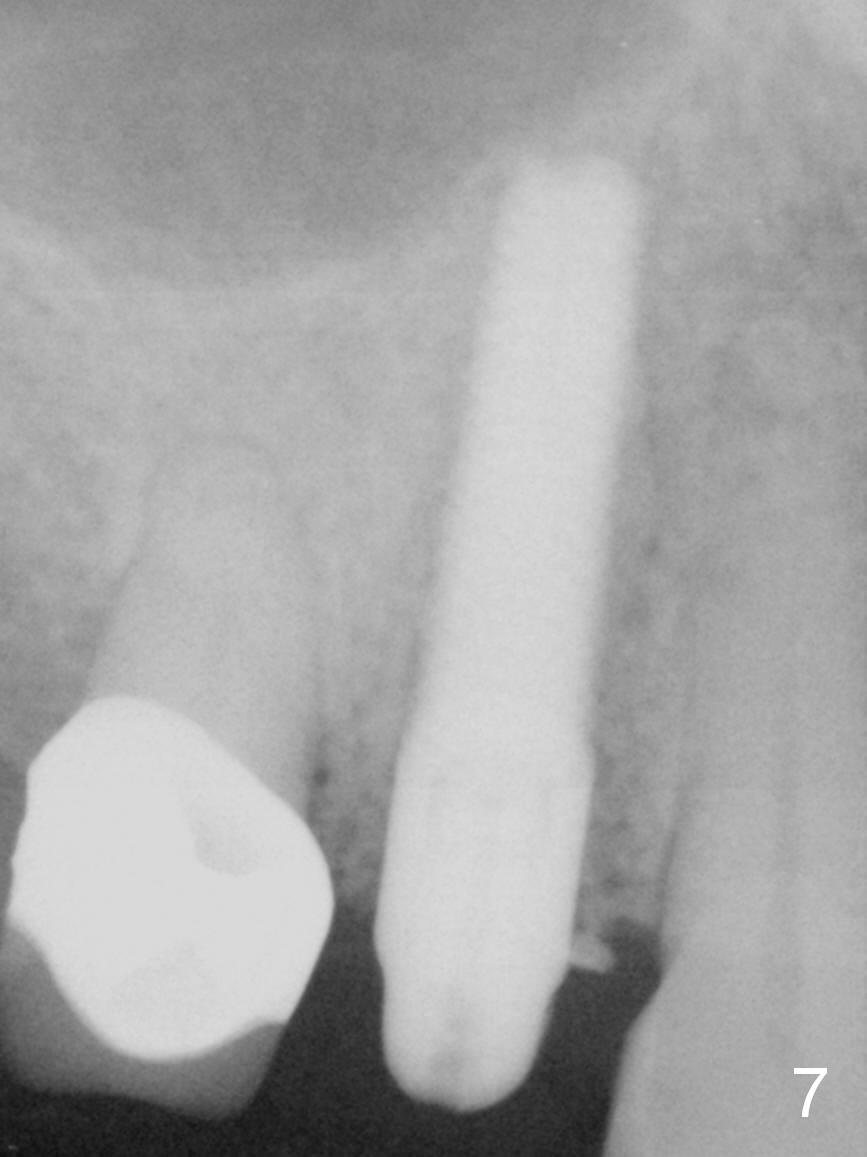

After long discussion, she agrees with extraction and immediate implant.  After the extraction, granulation tissue is removed.  There is buccal apical fenestration.  The socket is treated with Metronidazole.  The socket depth is 17 mm, while osteotomy depth is 20 mm (Fig.4).  A 4x20 mm tissue-level implant is placed with primary stability (Fig.5,6 I).  A short abutment (A) is placed immediately for an immediate provisional.  The buccal gap is filled with Osteogen plug.  There is no crestal bone loss 3 months postop (Fig.7).  The provisional stays in place with occlusal perforation.  The gingiva is healthy 5.5 months post cementation (Fig.8).